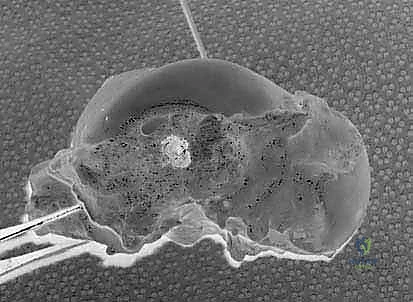

2. الفحص بالمنظار (Arthroscopy)

كخطوة أولى، ولضمان الدقة القصوى، غالباً ما يستخدم الدكتور هطيف منظار الكاحل عالي الدقة (4K Arthroscopy). يتم إدخال كاميرا دقيقة جداً عبر شقوق صغيرة (ثقوب) لفحص مفصل الكاحل من الداخل، تنظيف أي أنسجة ملتهبة، ومعالجة أي تلف في الغضاريف قد يكون مصاحباً للإصابة.

5. حفر الأنفاق العظمية وإعادة البناء (Bone Tunnels & Fixation)

هذه هي الخطوة الأكثر دقة هندسياً في الجراحة:

* يتم حفر أنفاق دقيقة جداً في عظمة الكعب الإنسي (قصبة الساق) وفي العظم الكاحلي وأحياناً العظم العقبي، وذلك في نفس نقاط الارتكاز التشريحية للرباط الدالي الأصلي.

* يتم تمرير الطعم الوتري عبر هذه الأنفاق بطريقة تحاكي تماماً شكل ووظيفة الأربطة العميقة والسطحية.

* يتم شد الطعم للدرجة الميكانيكية المثالية التي تضمن استقرار الكاحل دون تقييد حركته الطبيعية.

* يتم تثبيت الطعم بقوة داخل العظام باستخدام مسامير تداخلية (Interference Screws) أو خطاطيف معدنية/بلاستيكية قابلة للامتصاص (Suture Anchors) من أحدث الطرازات العالمية.